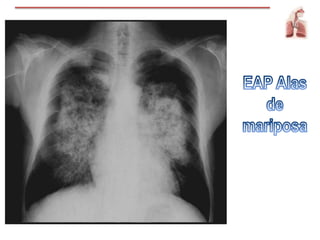

Radiografía de tórax

Bordes imprecisos

Imagen de mariposa

Cefalización

Líneas de Kerley

Oximetría / gasesarteriales Radiografía de tórax Bordes imprecisos Imagen de mariposa Cefalización Líneas de Kerley EKG / Ecocardiograma Lesión coronaria aguda Elevación de ST Aparición de onda Q significativa Hipertrofia ventrículo y/o atrio IZQ Marcadores de lesión cardiaca Cateterismo DER cardiaco